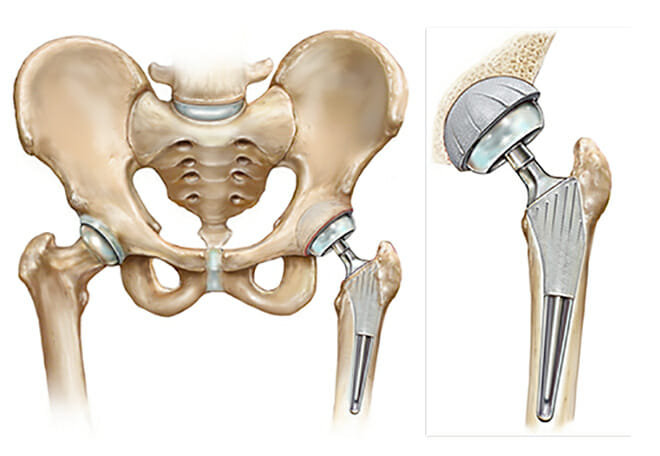

Total joint replacement:

Image Source: https://www.summitortho.com/services-2/joint-preservation-replacement/arthritis-related-conditions-treatments/total-hip-replacement/

In this procedure, the surgeon will remove the damaged joint and replace it with an artificial joint.